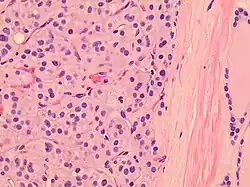

| Histopathology of a Hürthle cell adenoma | |

Hürthle cells are characterized as enlarged epithelial cells. These cells, when stained with hematoxylin-eosin show as pink. This is due to the abundant mitochondria and granular eosinophilic matter within the cells' cytoplasm. These cells are often found in the thyroid. The thyroid is a butterfly-shaped organ, responsible for producing various hormones for metabolism. These cells are often benign, but they can be malignant and metastasize. Hürthle cells are resistant to radiation, but can be treated using radioactive iodine treatment.[4]